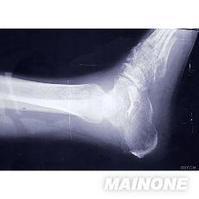

骨结核在X片上的表现[编辑 | 编辑源代码]

(一)骨质破坏

骨小梁模糊,似磨砂玻璃样的感觉,呈现出骨质缺损。其缺损区为局限性,边缘相对清晰,可有硬化,是为局限性结核病灶的特点,再继续以弥散性破坏加剧,易向髓腔拓展而形成结核性骨髓炎。骨质破坏易发生于骨骺及干骺,可在骨质中央部分亦可在边缘部分,形成缺损,往往骨骺及干骺同时破坏,形成不受骺板限制的统一破坏区。

关节骨质破坏,从两侧边缘开始,中央的关节板面较轻,是结核的特点。但在膝关节、肩关节中央部分亦可破坏,因紧密相接的软骨较少。关节骨质破坏上下相对应的关节板面同时受累。但这种接触面骨质破坏也不一定是为结核所独有。

肩关节结核的肱骨头呈现类圆形穿凿样改变。膝关节结核在胫骨上端关节板面两侧呈现小的穿凿样改变,耻骨结核在耻骨联合或耻骨板呈现类囊状或不规则的破坏。椎体结核以骨质破坏和椎间隙狭窄为主要表现。

常在骨端内或干骺端内见到,中央性破坏可形成囊状,亦可在短骨及块状骨见到,甚至在骶骨上显示囊状破坏区。

死骨的形成一般较多见的为细小的沙砾样死骨,常在松骨破坏区发现,如骨骺内,干骺内。髌骨结核亦常出现死骨,血供丰富的地方不易见死骨,如骨干结核、髂骨结核。有时在上下相对应的关节面都有死骨,常称之为接触性死骨。在膝关节内时有发生。

(二)骨形改变。管状长骨的破坏可表现为不同程度的膨胀变形,脊椎的椎体结核、椎体坍塌可呈楔状变形,椎体上下之间相互嵌入出现驼背或龟背畸形等。

(三)关节改变。关节软骨被破坏可使关节间隙狭窄,软骨破坏后不会再生,狭窄发生后会长期存在。脊椎椎间盘破坏不能再生,如破坏明显,椎间隙永久性消失